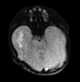

Abnormal septum pellucidum

Agenesis or hypoplasia of the corpus callosum

Neuronal migration disorder